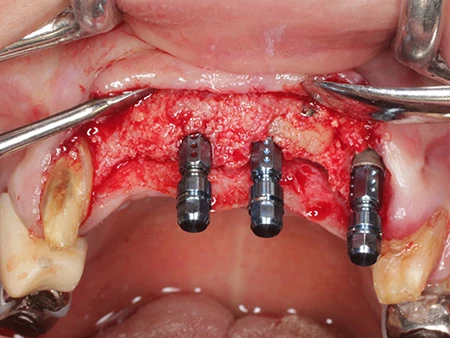

移植した骨が生着するまで6ヶ月待った後、インプラントの埋入を行います。

上顎前歯5本欠損に対してブロック骨移植とインプラント埋入(3本)